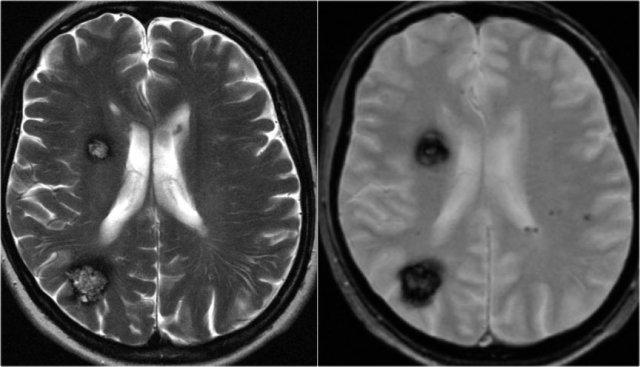

Chuỗi xung T2W và T2* gradient echo cho thấy nhiều cavernoma.

Lưu ý hình ảnh “bỏng ngô” với vành hemosiderin ngoại vi trên chuỗi xung T2W.

Các tổn thương gần như hoàn toàn màu đen trên chuỗi xung gradient echo do xảo ảnh blooming.

Chuỗi xung T2* và hình ảnh trọng số độ nhạy từ (SWI) làm tăng đáng kể độ nhạy của MRI trong việc phát hiện các cavernoma nhỏ.

Năm chấm đen ở bán cầu đại não trái trên chuỗi xung T2* cũng là cavernoma và không thể nhìn thấy trên chuỗi xung T2W.